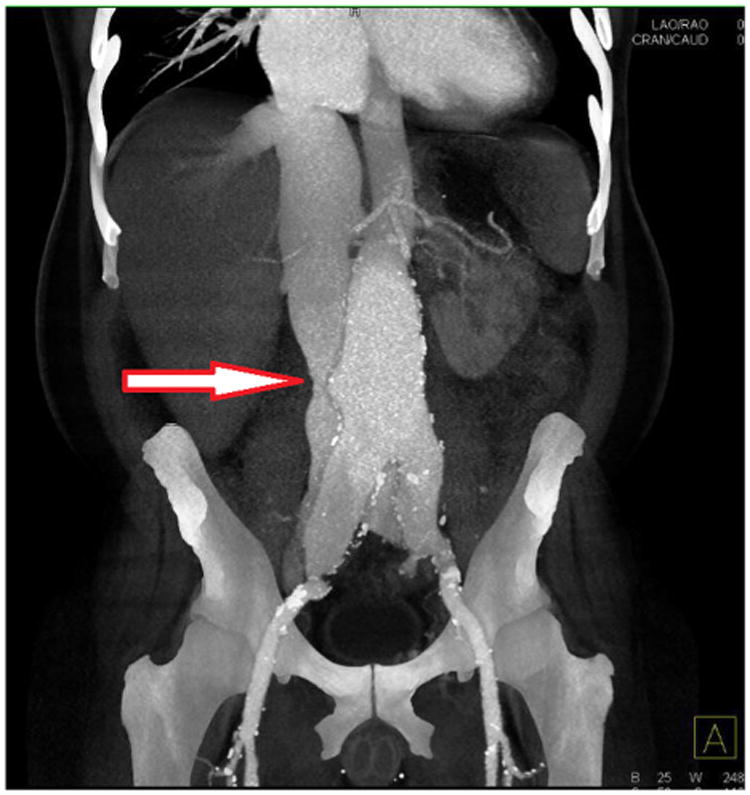

A 55-year-old African-American man with a 42-pack-year smoking history, coronary artery disease, and ongoing dyspnea was referred for an AAA. The patient underwent CT angiography which identified a 6.8-cm infrarenal AAA as well as bilateral iliac aneurysms, measuring 5.0 and 3.5 cm. More important, it also revealed a large ACF (Fig. 1). Previous echocardiograms showed a declining left ventricular ejection fraction (current left ventricular ejection fraction = 35%) and a dilated right ventricle with a pulmonary artery pressure of 70 mm Hg. A right heart catheterization was performed which demonstrated several residual 50–70% coronary stenosis but no lesions which would benefit from further percutaneous revascularization. The coronary arteriography also confirmed a massively elevated right heart filling pressure of 25 mm Hg. His overall deteriorating clinical condition was thought to be secondary to his progressive high-output heart failure and was taken semielectively for an open repair as the obligate delay for a fenestrated device to address his juxtarenal AAA would place him at undue risk for further functional decline. A pulmonary catheter was placed and transesophageal echocardiography performed (Fig. 2). Repair was approached via a generous midline incision during which time massive edema was noted throughout retroperitoneum. There was a thrill in the vena cava, and as the cava was compressed in that area, normalization of the right ventricular hemodynamics occurred. The aortoiliacs were controlled, and the aneurysm sac opened revealing a large ACF. Venous bleeding was controlled manually with compression within the aneurysm sac, and the ACF repaired primarily with running Prolene sutures from within the aortic wall (Video 1). Estimated blood loss was 2000 mL, and the patient received 750 mL of Cell Saver transfusion and 2 units of banked blood. After ACF closure, the patient's pulmonary artery pressures immediately decreased from 61 of 42 to 23 of 15. His heart rate was maintained; however, the patient was placed on a nitroglycerin drip for hypertension. The aortic and iliac aneurysms were repaired with a bifurcated Dacron graft, each distal limb to the iliac bifurcations. His postoperative course was uncomplicated. His cardiac output decreased from 12.0 L/min preoperatively to 5.6 L/min postoperatively. He was discharged home on postoperative day 7. At his 2-month check, he lost 70 pounds, and he was beginning to return previous activities such as swimming and weightlifting. At 1 year of follow-up, his echocardiogram demonstrates favorable remodeling and improved ejection fraction.

Fig. 1.

Three-dimensional reconstruction of CT angiography. White arrow, large aortocaval fistula.